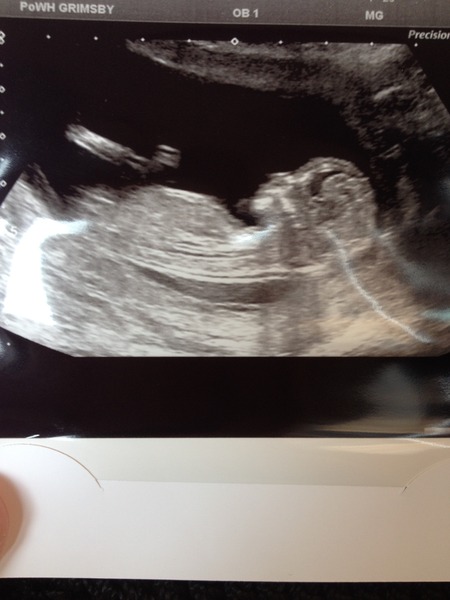

FranksBobot · 16/06/2014 16:00

All good at scan, 12+4 today so due Christmas Day. Baby moving loads (just like DD)

Hooray franks I've been checking in all day waiting to hear your news. Lovely pic too!

Lovely pic franks .